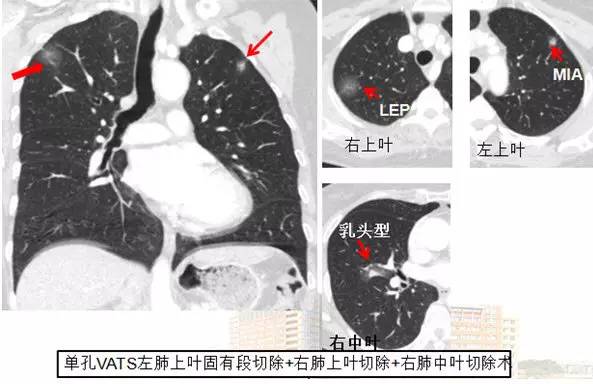

还有些病人是多个主病灶,分布在不同的位置,这种情况下,可以采用同期手术的方式,把它们一锅端,一次手术解决所有病灶。

4 个肿瘤一次全切除后,分别为 4 种类型的肺癌